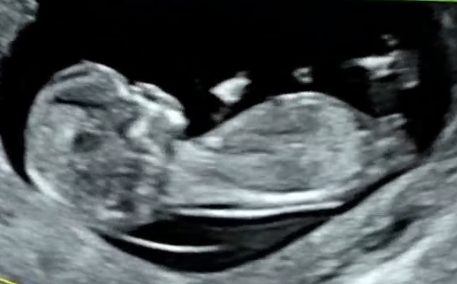

12주1일차 각도법 의견 부탁드려요~~

너무 너무 궁금해요 ㅠㅠ